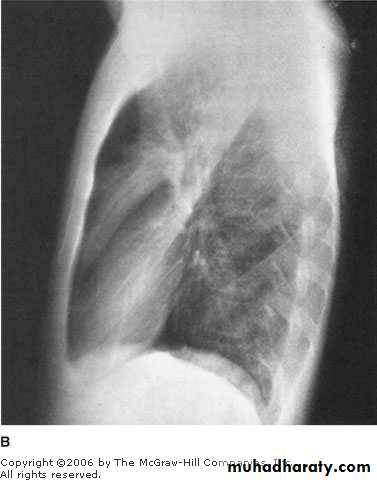

A 37 years old presented with chronic cough, fever and hemoptysis.He gave history of chronic steroid use for his poorly controlled asthma.

His chest X ray shown.

What is the most likely Dx?